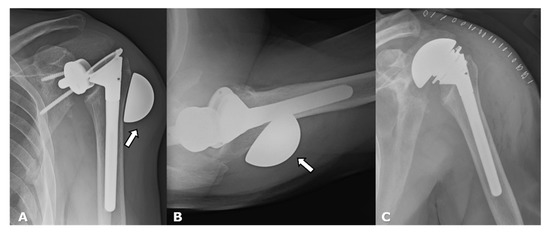

4.2.1. Loosening and Hardware Dissociation

4.2.2. Stress Shielding and Fractures